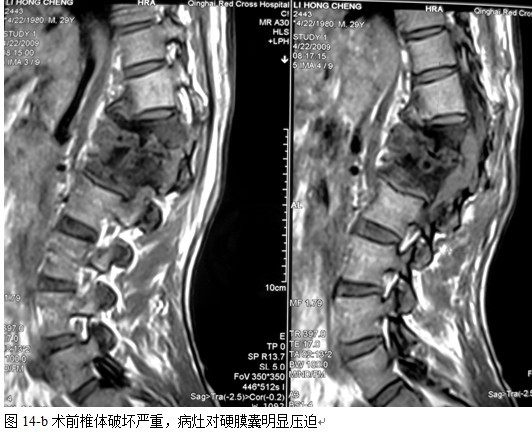

本组46例中男28 例,女18 例。年龄17~67岁,病程6 个月~7年,平均11.3 个月。本组患者均为 L1~S1腰段结核。病灶累及2 个椎体31例(L1-2 6例, L2-3 8例,L3-4 10例,L4-5 5例,L5-S1 2例),3 个或3 个以上椎体15例。合并腰大肌脓肿23列,所有患者均有腰背部疼痛,活动受限,双下肢感觉麻木19例,会阴部感觉减退12例,双下肢肌力减弱12例,腱反射减弱12例,术前后凸角(Cobb 角) <30°者12例, 30°~60°者28 例, >60°者6 例,Cobb角平均32.3°4例患者是二次手术。术前均行X线片、CT或者MRI检查。术后病理检查确诊为脊柱结核。

本组手术用时间3~4h , 平均3.5h 。术中出血300~500ml , 平均约350ml 。术后症状完全缓解,无神经功能障碍加重等并发症,1例营养差的老年患者伤口出现窦道,1例因肝功能差,术后未口服抗痨药,伤口出现窦道,经换药后二期愈合,其余病例伤口均一期愈合。马尾神经受损的患者术后基本恢复正常。术后一周后凸角平均 5.4°后凸畸形平均矫正90%以上, 最终后凸角平均8.3°,后凸角度平均丢失4.2°。随访3个月有87%(40/46)有骨痂形成,6个月91.3%(42/46)明显骨性愈合(见图),其余4例9-12个月内愈合,随访时间3-32个月,平均11个月,46例患者中2例在术后2个月和3个月时背部形成脓肿,换药后治愈。2例出院1月后并发结核性脑膜炎,治疗后好转。1例因椎弓根钉偏外,刺激神经根,5个月后从侧方脱出,疼痛加重,因前后路植骨完全愈合,取出后症状完全缓解。

脊柱结核手术治疗的传统术式是病灶清除椎管减压术。其目的是清除病灶及椎管内脓汁、干酪样坏死物、死骨,保障抗痨药物的渗透,促进病灶愈合,解除脊髓压迫。不足之处在于死骨不能完全清除的可能,残留椎间盘不能完全清除的可能。凿开病灶清理后椎体间残留空间大,前中柱结构的破坏和缺失,造成脊柱不稳,后凸畸形加重的可能,造成迟发型神经损伤的可能且植骨块在压力状态下再度脱落吸收的可能性较大。在结核病灶内使用内置物的安全性已经得到实验及临床研究的证实[9、11],内固定的应用使脊柱结核的手术治疗取得了很大进步,但在手术方式的选择上,选择前路病灶清除植骨内固定,还是一期后路经椎弓根内固定结合前路病灶清除植骨融合,目前仍有争议[12、13、14、15、16、17、18、19、20、21],选择前者的学者认为通过一个入路,一次完成所有手术操作,可以避免再行后路内固定的手术创伤,而且椎间植骨的融合率较后外侧融合率高,但前路暴露创伤大,内固定的植入存在一定的风险和困难,前路内固定主要重建脊柱的前中柱,前路内固定适于1-2椎体的的破坏,对于多个椎体的结核前路的手术效果较后路差。选择后者的学者认为,后路固定可以避免在病灶内应用内固定,安全性更有保障,但需要两个切口,创伤大,术中需改变体位,而我们的方法取其两者的优点,只有后侧单一切口,创伤相对小,置入椎弓钉相对容易,而且后路椎弓根钉棒系统固定为三柱固定,作用强大,在清除病灶时,我们选择有脓肿,破坏严重,神经症状重的一侧,通过关节突关节,采用刮,凿,切,咬等方法逐步彻底清除病灶,用椎体撑开器逐步撑开椎间,这样更有利于后凸畸形的矫正。对于前方病灶对硬膜压迫较重的患者,只能先行前路病灶清除,撑开时不必担心前路病灶对的压迫病灶完全清除后,准备植骨床,前路植骨后,可对植骨块用椎弓根系统加压,使其更为稳定。另一侧椎板和关节突处可植入碎骨,融合率明显提高,对于脓肿我们首先充分引流,然后用长的刮勺刮除脓肿壁的脓胎,再用干纱布反复擦拭,只到有大量的出血点,再反复用异烟肼与盐水的混合液加压冲洗创面,可以降低局部的细菌量,最后经皮在病灶中放置硬膜外管,术后注射异烟肼,可以提高局部化疗药物的浓度,减轻毒副反应,对于降低病变的复发也有很大作用。

中国学者金大地[22]等采用一期前路病灶清除植骨前路钢板固定治疗腰椎结核,平均18°的后凸畸形得以矫正,Mukhtar[23] AM等采用前路病灶清除植骨分期或同期后路固定治疗腰椎结核22例,术后后凸畸形矫正度数平均为27°。从我们的随访结果看,术后后凸畸形平均矫正度数为26.9°,后凸畸形平均矫正90%以上, 6个月-49个月后随访,后凸角度平均丢失4.2°。本术式也适用于结核所引起的弹性差的后凸畸形,对于病灶纤维化或骨化的非弹性后凸畸形,后路固定后,先行前路病灶、纤维化或骨化切除、松解,逐步刮除病灶、逐步撑开,达到畸形矫正和植骨的目的。